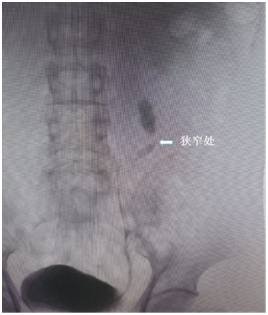

入院后行逆性肾盂输尿管造影提示输尿管狭窄段位于输尿管上段,狭窄段长约1cm。

狭窄段输尿管管腔消失